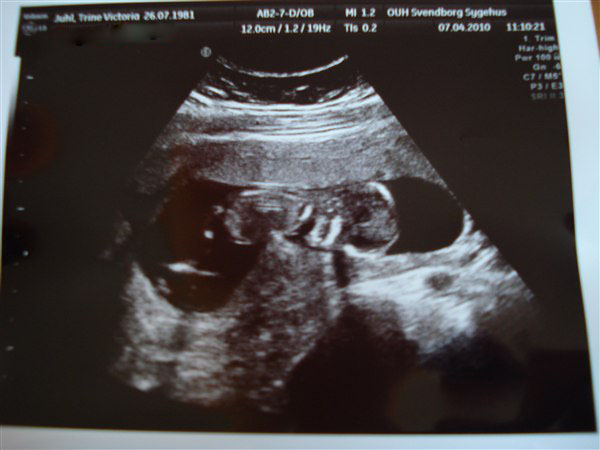

og lige på det første billede kunne vi allesammen med det blotte øje se, at nakkefolden var meget meget tynd. men så blev lægen så ivrig efter at vise os hvor fin den var, at han glemte at tage billede, så han måtte scanne og scanne og scanne og jeg måtte flere gange løfte bækkenet og vrikke med måsen og til sidst kom sygeplejersken og forsøgte og så fik de den endelig målt. da de så havde tastet alt ind i systemet udbrød de begge to "ja, det er meget, meget lavt!" og smilede over hele femøren. "din termin bliver rykket til 13. oktober (på Carlas fødselsdag) og din baby har det rigtig godt, tallet er 1:15000, det er en meget meget meget lille risiko"

I får lige et par snapshots, den ligger ligesom på maven med hovedet ude til venstre: